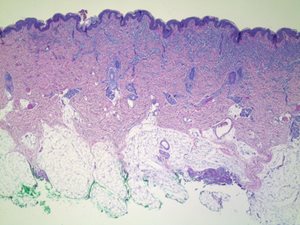

A healthy 21-month-old male infant presented with a tan-brown nodular lesion on his left anterior chest wall and a hairless, brown patch on his scalp. A surgical excision was performed.

Figure 1: H&E 20X